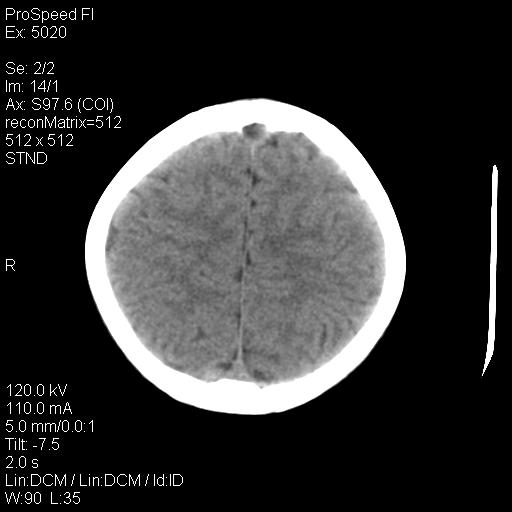

标题: PED1637:M 6Y 顶部无痛性包块两月。 [打印本页]

标题: PED1637:M 6Y 顶部无痛性包块两月。

1、年龄--6岁

2、颅骨局部缺失,边缘光滑、整齐

嗜酸性肉芽肿是郎罕氏细胞增多症的一种表现,以前称为组织细胞增多症x。嗜酸性肉芽肿多发生于5-10岁的儿童,侵犯部位为骨骼和肺。

颅骨为好发部位,生长缓慢,常位于顶骨、枕骨及颞骨,表现为颅骨缺损,呈圆形或椭圆形,边界清,无硬化